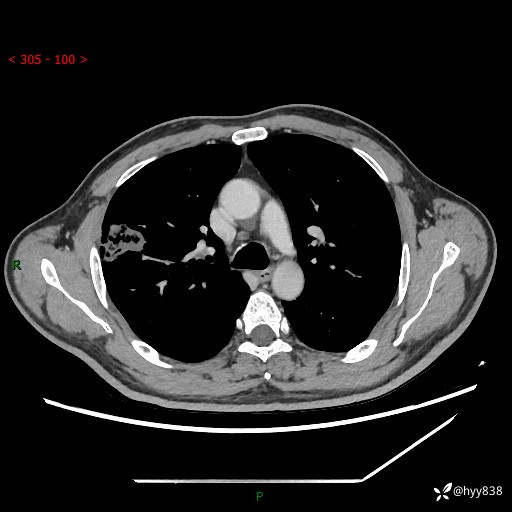

现病史:患者2天前体检完善胸部CT提示:右上肺团块影,炎症可能,肿瘤性病变不除外,冠状动脉钙化,无咳嗽、咳痰,无寒战发热,无恶心、呕吐等其他特殊不适,未予以特殊治疗,现为明确病变性质来我院就诊,门诊以“肺肿物性质待查”收入我科。 起病以来,患者精神、饮食、睡眠可,大小便正常,体力体重较前无明显变化。

胸部CT平扫+增强